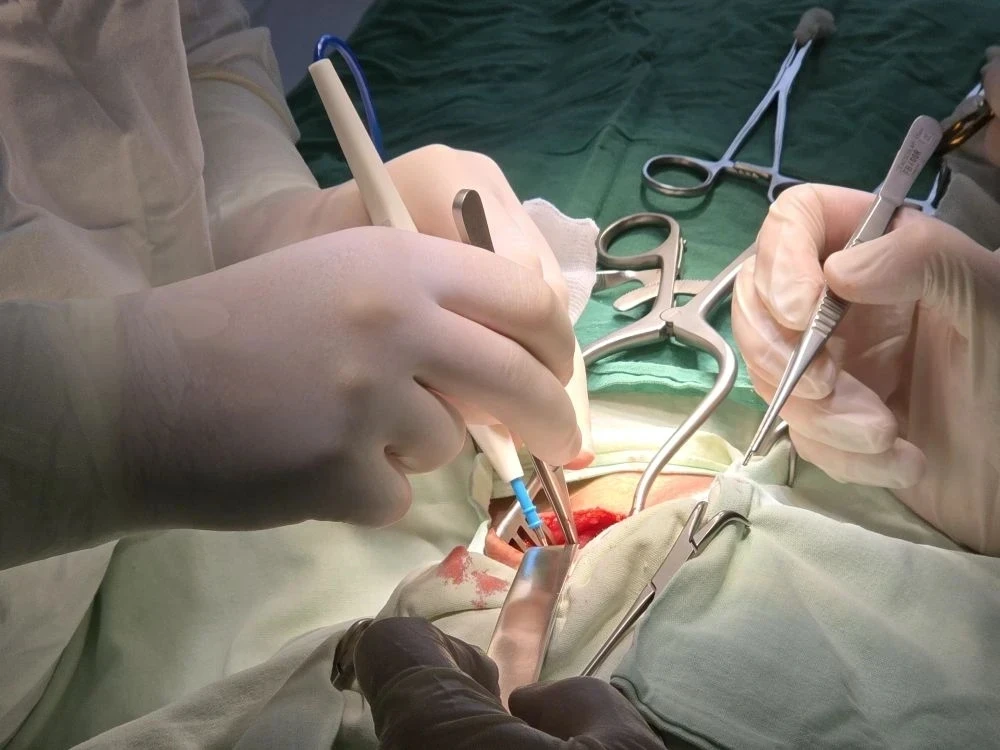

Каротидная эндартерэктомия (КЭАЭ)– уже более четверти века является одним из самых эффективных и безопасных методов хирургического лечения, помогающих предотвратить ишемический инсульт. Восстановление после вмешательства занимает не более трех дней.